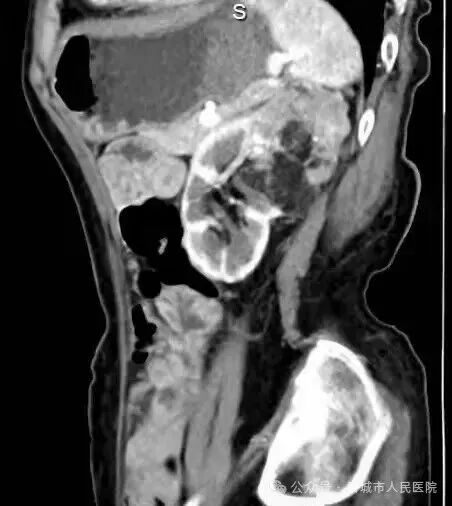

据了解,患者因体检发现左肾占位20余天入院,外院检查提示左肾肿物大小约45*55*98mm,接近十公分的肿瘤体积给治疗带来了极大挑战。更为棘手的是,患者年事已高,体质薄弱且营养状况欠佳,腹壁肌肉薄弱导致手术戳卡固定困难,传统腹腔镜手术操作空间受限、难度极高,而患者及家属保肾意愿十分强烈。